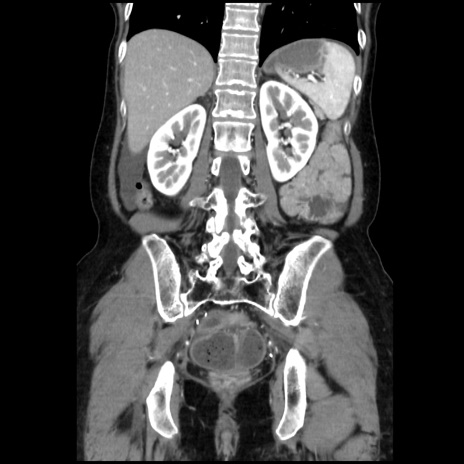

症例32(冠状断像)

【症例】40歳代 女性

【主訴】上腹部痛、嘔気・嘔吐

【現病歴】約9時間前頃から急に上腹部痛、嘔気、嘔吐が出現。改善しないため救急要請。

【既往歴】子宮頚癌(広汎子宮全摘術、放射線療法)、腸閉塞

【身体所見】腹部:平坦、軟、腸雑音亢進、上腹部を中心に腹部全体に圧痛あり。

【データ】WBC 8400、CRP 0.03